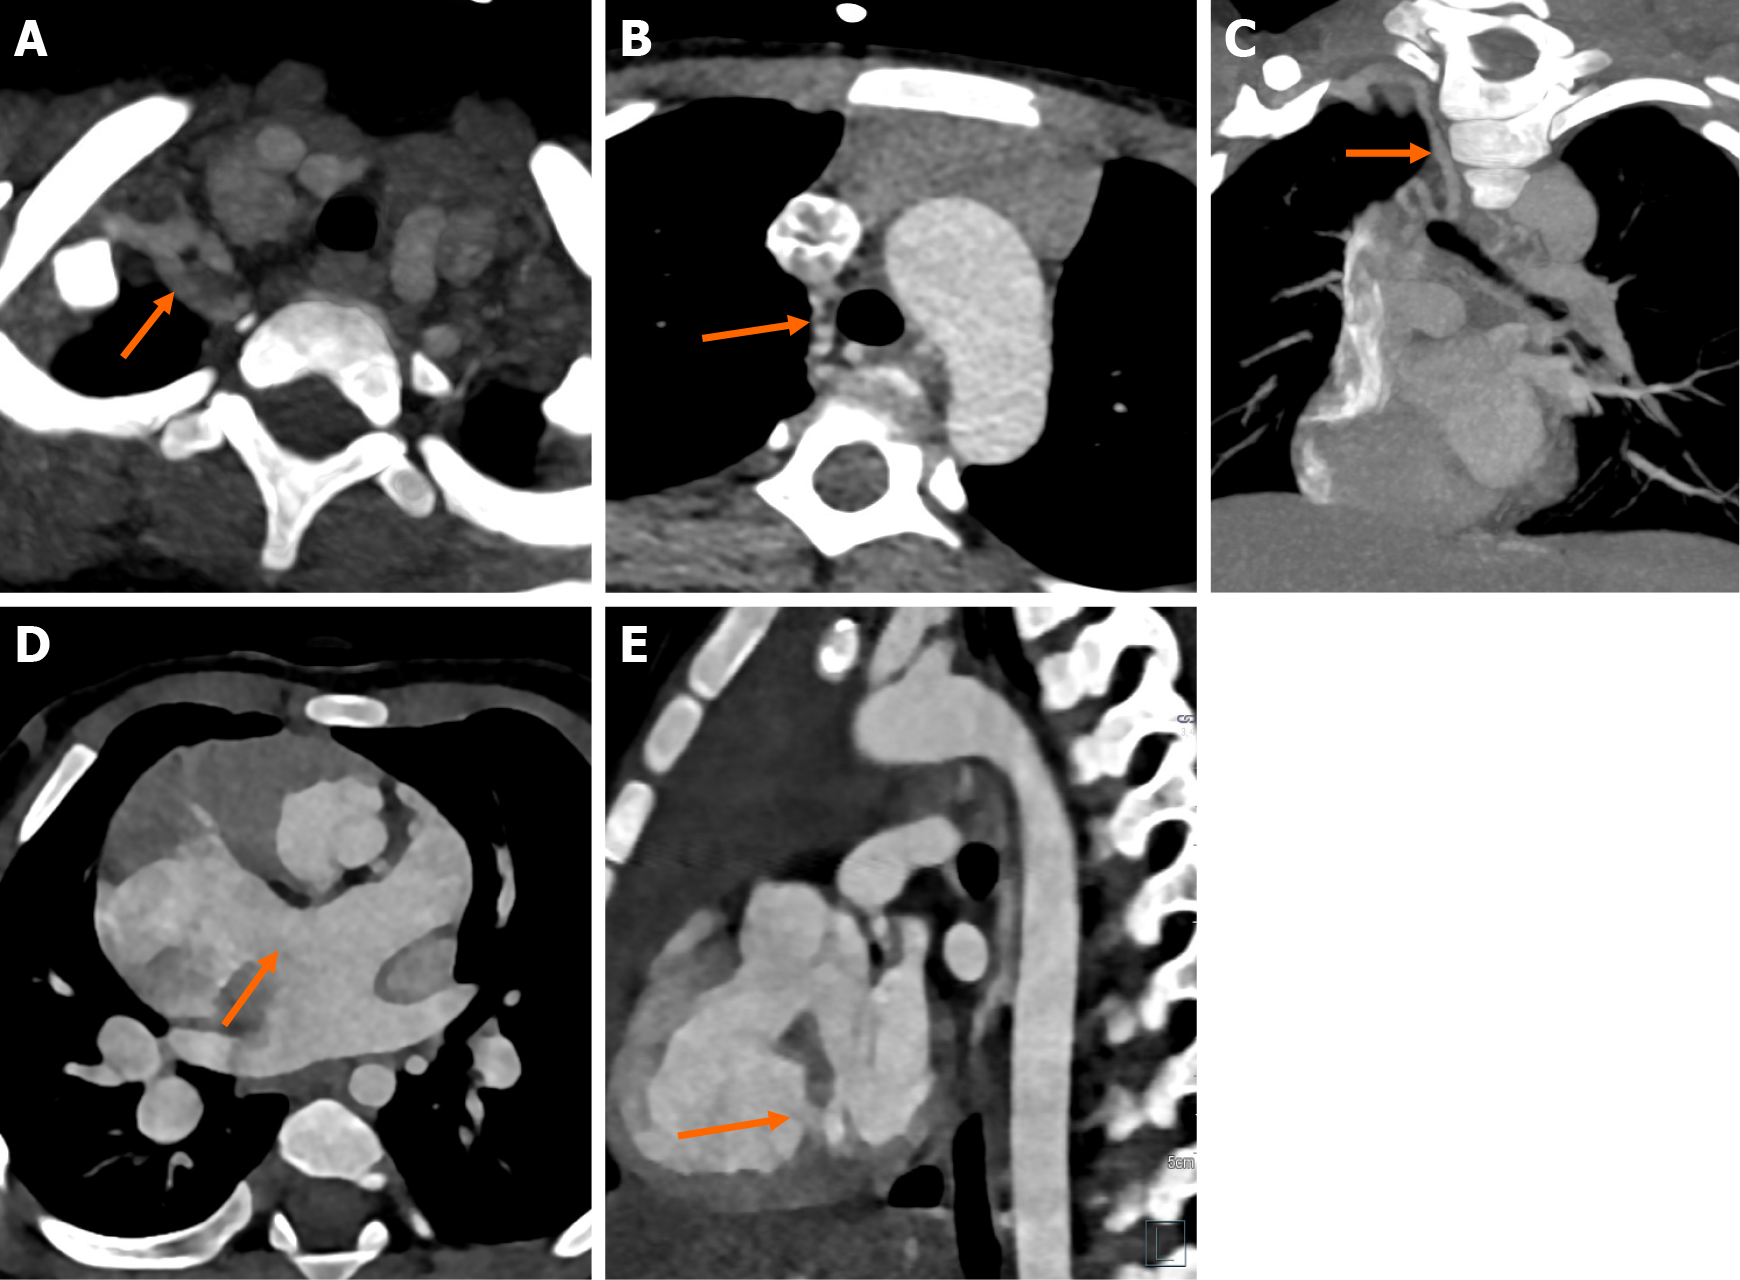

Figure 8

Figure 8 Computed tomography images. A-C: Axial (A and B) and coronal reformatted images (C) of computed tomography angiography in a child with tetralogy of Fallot showing systemic aortopulmonary collateral artery in the right paratracheal location arising from the right subclavian artery and reforming the right pulmonary artery; D and E: Axial image of computed tomography angiography showing a large atrial septal defect in a patient with tetralogy of Fallot consistent with pentalogy (D); Sagittal reformat of another patient showing a small muscular ventricular septal defect (block arrow) in addition to the perimembranous ventricular septal defect (E).

Aortic arch variations are commonly encountered in association with TOF. Right-sided aortic arch with mirror-image branching is the most common variation, present in 13%-34% of TOF patients. Among the supra-aortic anomalies, the bovine branching pattern is the most common, followed by the aberrant subclavian artery[44,45]. Associated visceral, pulmonary, and skeletal abnormalities can also be ruled out on CTA. The reporting template is provided in Table 3. Cardiac CT with three-dimensional reformation is often commonly used for postoperative evaluation. CT is an excellent modality to assess shunt patency, assess the vessels, and intracardiac anatomy. CT is limited for ventricular volumes and function[46-50]. Patent shunts are well-opacified on CT, whereas thrombosed shunts show hypodense filling defects (Figure 9).

Figure 9

Figure 9 Operated patient with tetralogy of Fallot. A-C: Axial computed tomography images of a postoperative patient with tetralogy of Fallot. Perimembranous ventricular septal defect (asterisk) (A). Infundibular pulmonary stenosis (arrow) with atresia of the main pulmonary artery (B). Central aortopulmonary shunt (arrows) between the ascending aorta and main pulmonary artery (C); D-F: Oblique Coronal reformat in an operated patient of tetralogy of Fallot. Showing patient modified-Blalock Taussig shunt between the right subclavian artery and the confluence of branch pulmonary arteries(D). Coronal reformat of another patient showing patent right Glenn shunt between the superior vena cava (SVC) and right pulmonary artery (E). Another patient with tetralogy of Fallot and double SVC showing bilateral Glenn shunts from both the SVCs to the branch pulmonary arteries, with a patent right shunt and partial thrombosis of the left shunt (F).